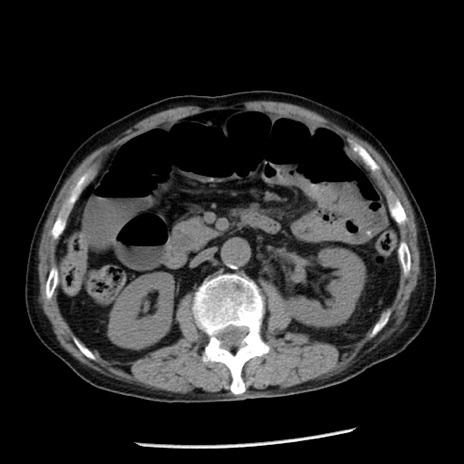

冠状断像

症例26(横断像)

【症例】80歳代男性

【主訴】嘔吐

【現病歴】昨晩2回嘔吐あり、今朝になっても嘔吐あり。来院。

【既往歴】胃潰瘍

【身体所見】意識清明、BT 37.6℃、BP 166/95mmHg、HR 100bpm、SpO2 97%、腹部:平坦・軟、腸蠕動音聴取良好、圧痛なし。

【データ】WBC 21900、CRP 1.46